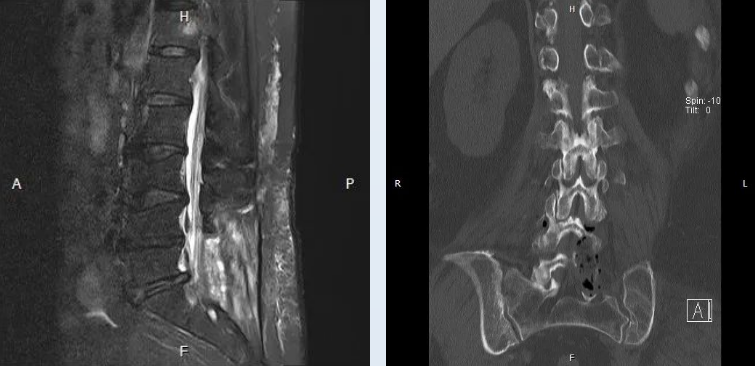

住院后,神经外科程扬主任精心为患者进行细致查体,并完善了腰椎CT及腰椎核磁共振等检查;最终患者被初步诊断为:腰椎间盘突出,继发椎管狭窄。

随后,王贵怀教授与程扬主任制定了详细的手术方案,拟在显微镜下行后路腰4-5扩大椎管减压、神经根管减压术。术程顺利,术中通过彻底磨除腰4、腰5、骶1椎骨左侧椎板,来达到减压效果。术后,困扰患者2年多的症状得到了明显好转。